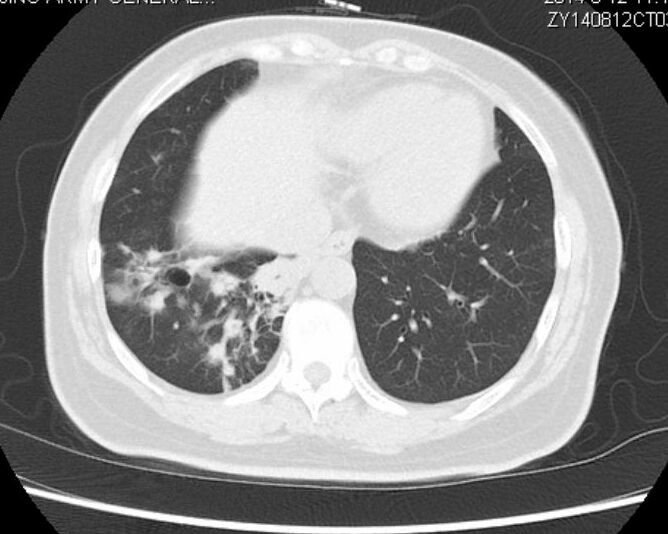

以下是第50个月的时候复查:

与两年前对比,病灶有所增大,但未影响肺功能,老太太总体状态很不错!

该患者在确诊时已经属于肺癌晚期伴有多发转移,最后一次随访时,已经带瘤生存50个月。